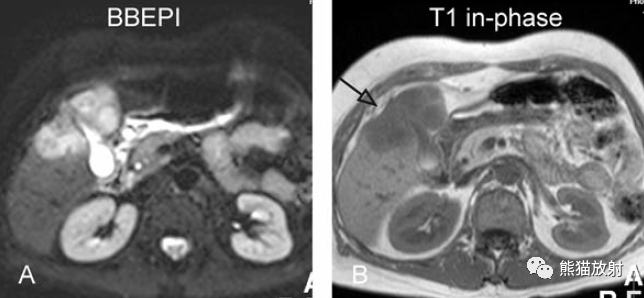

T2壓脂(T2 fatsat):膽囊窩內(nèi)膽囊癌病變較肝臟為高信號,病變頂部向肝內(nèi)擴(kuò)展;

T1同相位(T1 in-phase):膽囊癌病變較肝臟為低信號;

增強(qiáng)動(dòng)脈期(ART):不均質(zhì)強(qiáng)化;

延遲期(DEL):部分廓清,部分持續(xù)強(qiáng)化。

膽囊癌。A~D圖:上方層面,表現(xiàn)如上所述,形成腫物侵及肝臟。E、F圖:下方層面示膽囊壁不規(guī)則增厚,明顯不均質(zhì)強(qiáng)化。